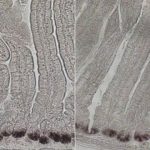

Study: Biologists find a way to boost intestinal stem cell populations — (Details)

Cells that line the intestinal tract are replaced every few days, a high rate of turnover that relies on a healthy population of...